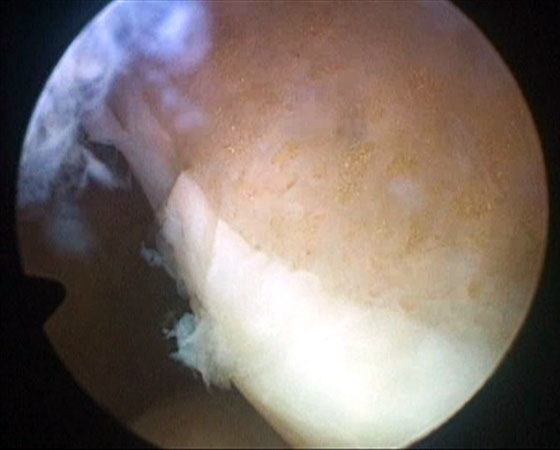

Se procede luego a realizar el portal posterointerno. Dado que no se reseca el remanente HPM, el espacio para acceder a la cápsula posterointerna se encuentra reducido, para ampliarlo realizamos una mínima “notchplastia” en la parte posterior del cóndilo interno (Fig. 4). Con la visión desde el portal anterointerno colocamos un switcher, de los utilizados en cirugía de hombro, desde el portal anterolateral ubicándolo entre el remanente ligamentario y el cóndilo interno (Fig. 5). Luego se pasa la cánula de irrigación guiada por el switcher y se accede con la óptica a la cápsula posterointerna, bajo visión directa colocamos una aguja espinal para localizar el portal, completando con bisturí para luego colocar la cánula de trabajo (Fig. 6). En este punto se vuelve a pasar el artroscopio al portal anterointerno, se introduce el shaver por la cánula del portal posterointerno, y se realiza la limpieza de la capsula posterior, siempre con la hoja de corte hacia anterior para evitar la lesión de estructuras vasculonerviosas. Se continúa alternando los portales anterointerno y posterointerno con visión, shaver, pinza basket y raspas de 90º, hasta completar la desinserción de cápsula posterior e identificar el remanente distal del ligamento sin afectar la inserción. En los casos en que la lesión ha sido en la sustancia colocamos la guía tibial distal a la inserción tibial (Fig. 7). Si la lesión ha comprometido la inserción tibial, levantamos la cicatriz que encontremos y colocamos la guía por debajo del remanente (Fig. 8). Para la introducción de la guía sin lesionar los remanentes ni el LCA se coloca la óptica en el portal anteroexterno y se controla el ingreso de la guía por el espacio entre el remanente y el cóndilo interno (Fig. 9). Se pasa el clavo guía, siempre cuidando de llegar en forma motorizada hasta contactar la cortical posterior y se completa el pasaje golpeando con martillo para evitar una salida brusca del mismo. Se pasa la fresa canulada del diámetro adecuado, protegiendo la emergencia de la misma con una cureta. Una vez completado el túnel tibial, se pasa un alambre o cable desde el orificio externo tibial hacia proximal, con visión en portal posterointerno, al ver emerger el alambre o cable por el orificio tibial posterior, se vuelve la óptica al portal anterointerno para controlar el pasaje de un grasper desde anteroexterno a través del intervalo entre HAL y LCA, y dirigirlo hacia posterior (Fig. 10); se vuelve con la óptica al portal posterointerno y se visualiza la recuperación del alambre o cable con el grasper hacia la parte anterior de la rodilla (Fig. 11). Se amplía el portal anteroexterno y se anuda la sutura tractora del injerto al alambre o cable, y traccionando desde el orificio distal del túnel tibial se hace ingresar el injerto en forma retrógrada a la articulación y, luego, al túnel tibial por su orificio posterior. En caso que se utilice el injerto de tendón cuadricipital la parte tendinosa irá al túnel tibial y el bloque óseo al femoral. Una vez ingresado el injerto al túnel tibial, se vuelve la óptica al portal anterointerno, en el portal anteroexterno tendremos la sutura tractora del extremo “femoral del injerto”, es aconsejable en este punto llevar el injerto lo más distal posible para tener mejor visión articular, enhebrar la sutura tractora en una cánula de unos 6 mm de diámetro, para asegurarse que la sutura tractora y la clavija pasasutura pasan por el mismo espacio sin incluir tejido sinovial o grasa retrorrotuliana (Fig. 12). Se procede a pasar la aguja pasasutura por el túnel femoral, saliendo por las partes blandas de la parte medial de la rodilla, se tracciona y se asciende el injerto colocándolo en el túnel femoral. En caso que el injerto tenga bloque óseo puede ser necesario redirigir el mismo para ubicarlo en el túnel femoral, para esto ubicamos la visión en el portal anteroexterno y por el portal anterointerno utilizamos el trocar romo o el palpador para realizar una polea y mejorar la tracción para que ingrese el taco óseo en el túnel femoral (Fig. 13). Luego se realiza la fijación femoral con tornillo de interferencia de titanio o biodegradable. A continuación liberamos el manguito neumático, porque creemos que produce un espasmo en los isquiotibiales que dificulta la reducción de la tibia, dejamos pasar unos minutos que utilizamos para colocar un tornillo maleolar con arandela, distal al orificio externo del túnel tibial para realizar una segunda fijación de la parte tibial. Preferimos hacerlo antes de colocar el tornillo interferencial, porque esto generará una presión hacia posterior de la tibia. Se realiza la reducción tibial en 90° de flexión de la rodilla, se tracciona del injerto y se coloca el tornillo de interferencia tibial, luego la sutura remanente (polyester 5) se anuda en el tornillo maleolar completando la 2da fijación. Por último se constata con una nueva visión articular la posición y tensión del injerto (Fig. 14).

Figura 6